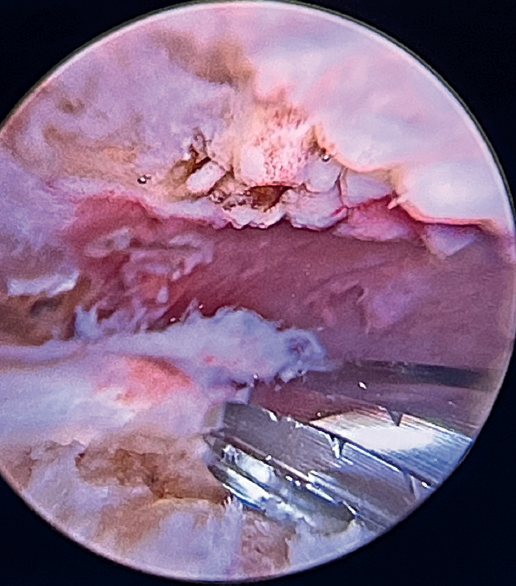

Tension-free repair of the supraspinatus tendon is then made, using the free thread left at the anchoring and taking advantage of the two sutures passed through and knotted to the proximal LPB fragment (Figures 8, 9 and 10).

The free suture remaining at the anchoring is passed through the anterolateral supraspinatus using a Scorpion® direct suture passer (Arthrex, Naples, FL, USA), as a sliding mattress suture over the implant.

One end of each of the sutures exiting the LPB is passed through the supraspinatus likewise using a Scorpion® direct suture passer (Arthrex, Naples, FL, USA). All the threads are left unknotted and are recovered through the anterior working portal so that they do not get in the way when working later on. Note that the two threads exiting the LPB and passing through the supraspinatus will not slide; it is therefore advisable to knot them and lower them later on with a knot pusher. This point allows repair of the anterior supraspinatus to be combined with fixation of the LPB in the anterolateral zone of the greater tuberosity.